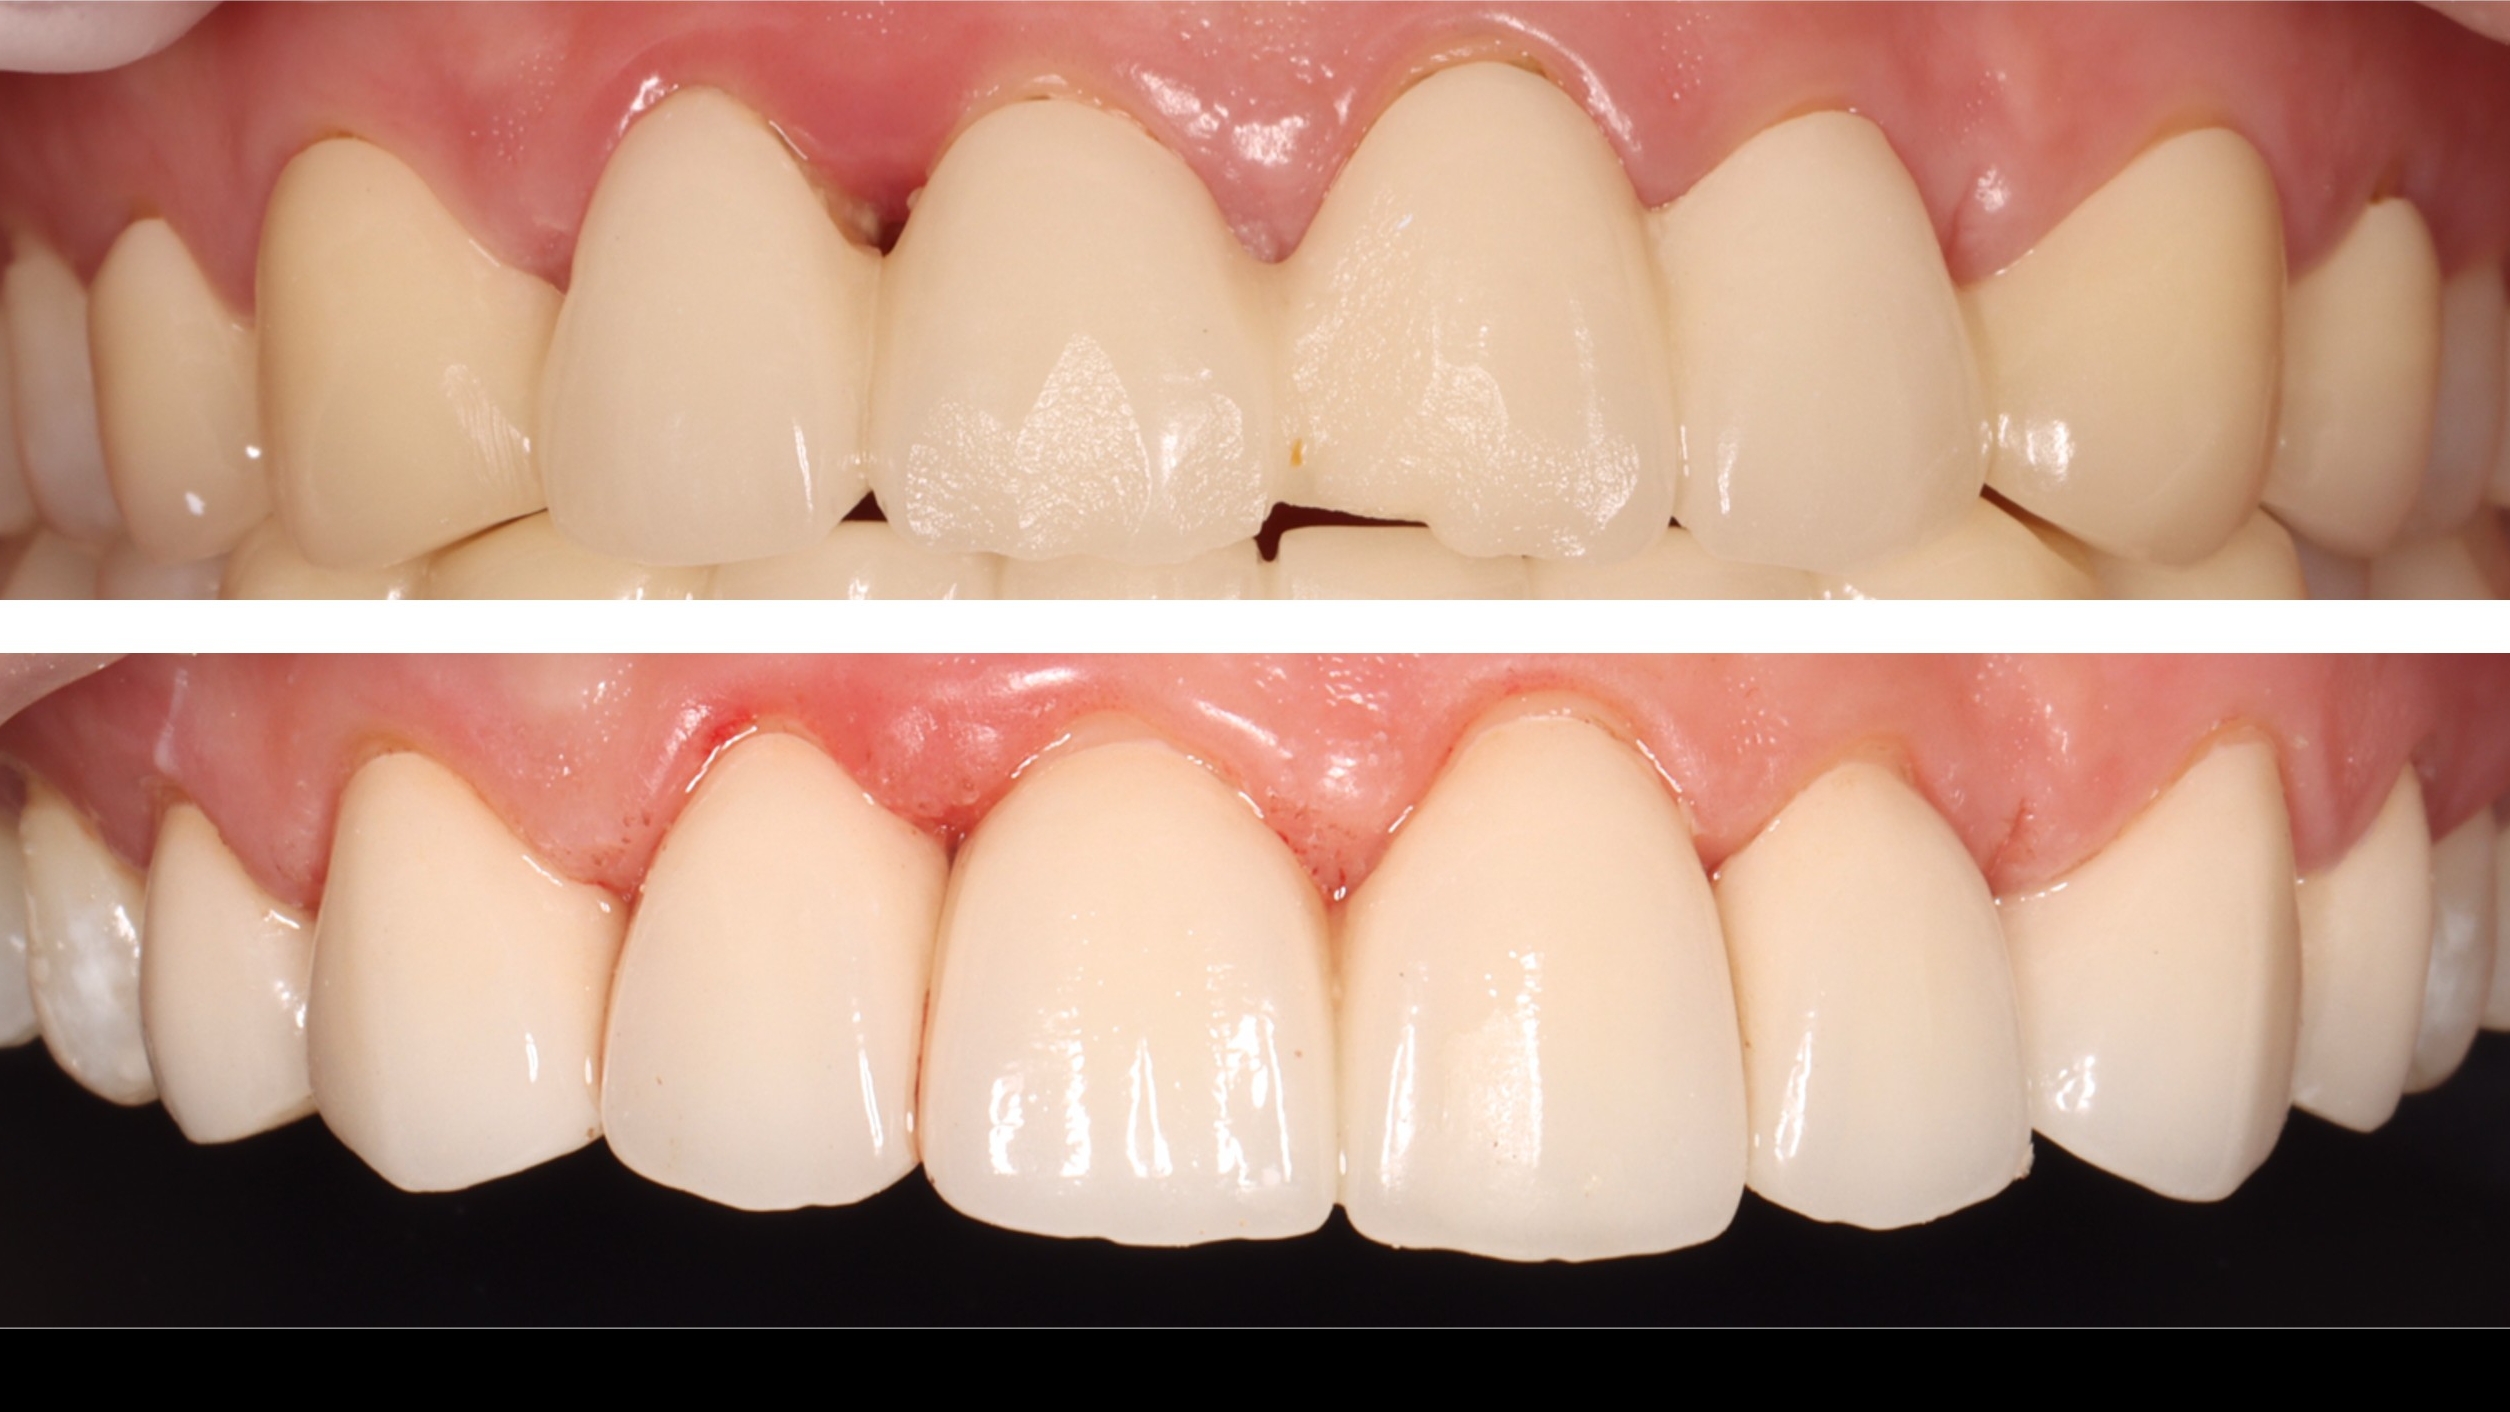

September 19, 2025: Delivery of zirconia post and core + all-ceramic crown for tooth 15; the margins are well-adapted with no occlusal high points, and the patient reported comfortable occlusion.

Post-delivery evaluation: Delivery of zirconia post and core + all-ceramic crown; the margins are well-adapted with no occlusal high points, meeting clinical restoration standards.

This is a typical case of severe tooth structure defect restored with zirconia post and core,

aiming to restore tooth function and aesthetic appearance.